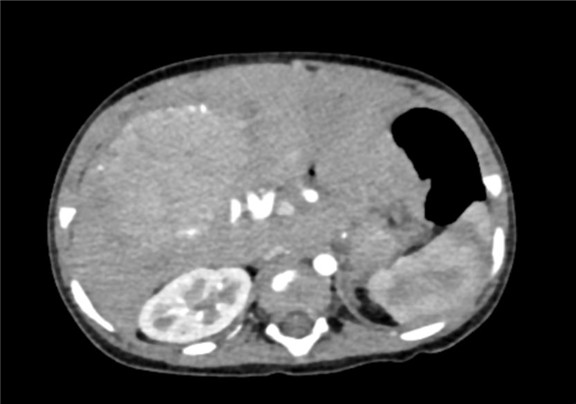

术前CT检查:

静脉期

下腹部增强CT示:肝内巨大占位,考虑肝母细胞瘤可能性大,建议MRI平扫+增强进一步检查,腹腔、腹膜后多发肿大淋巴结影,考虑转移瘤可能性大,肝内多发结节,考虑血管瘤可能性大,建议随访